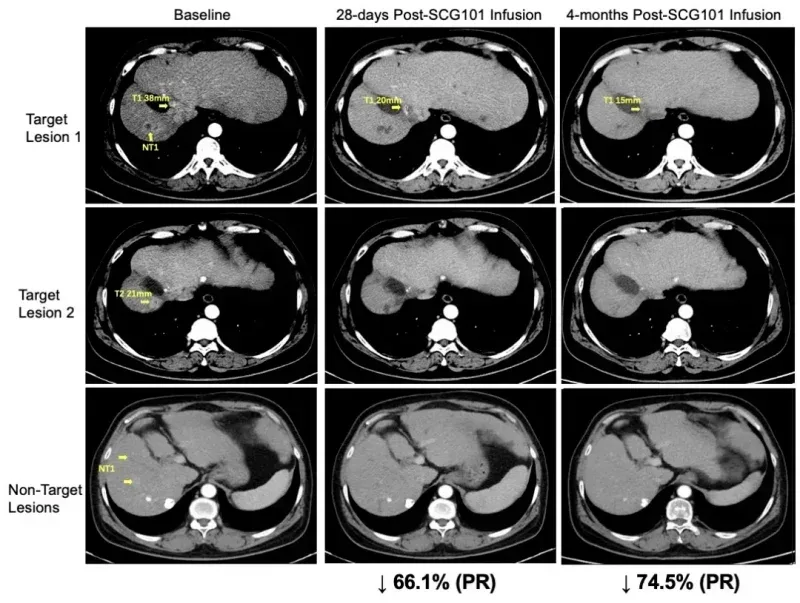

此前在2023年法国巴黎国际细胞与基因治疗大会(ISCT)上,还曾公布过SCG101治疗HBV相关肝细胞癌的突破性案例:一位患者接受单剂治疗后,实现肿瘤缩小与HBV病毒清除的“双向逆转”。

结果显示:治疗第28天,患者肿瘤靶病灶较基线缩小66%,达成部分缓解(PR);第4个月肿瘤进一步缩小至74.5%,一处病灶完全消失,截至数据统计时无进展生存期已超6.9个月,持续维持缓解。

此外,肝脏免疫组化显示,回输的SCG101 TCR-T实现100%清除乙肝表面抗原阳性肝细胞;血清学指标显示,HBsAg水平从输注前557.96IU/mL降至第7天1.3IU/mL、第28天0.08IU/mL,近乎清零。